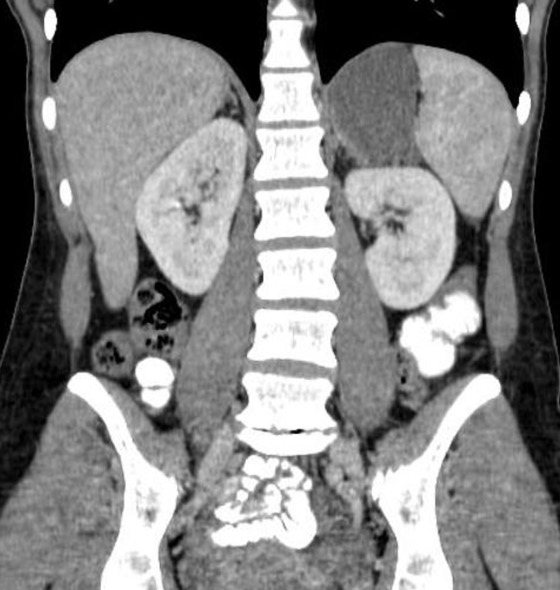

4) In this patient with sickle cell disease the most likely diagnosis is?

lymphoma

renal cell carcinoma

renal abscess

MEST tumor